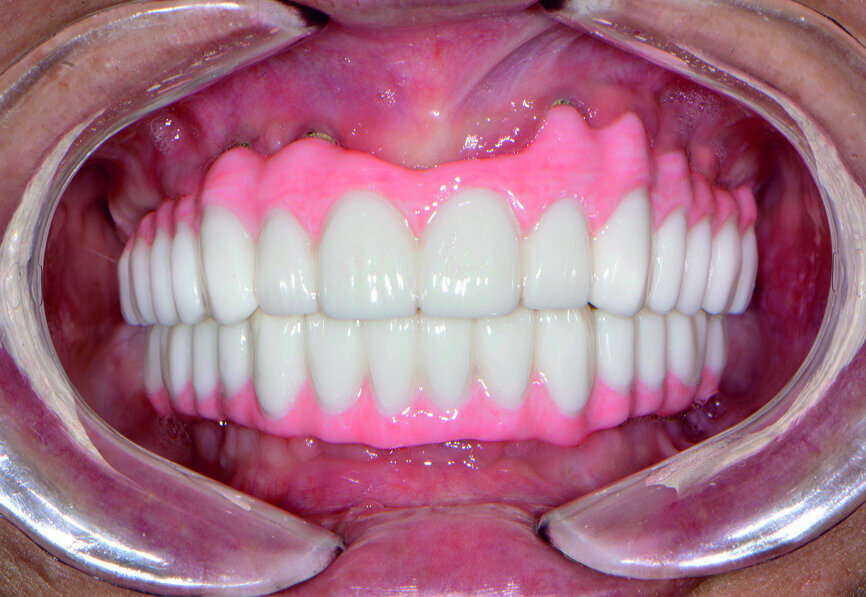

Fig. 21: Post-op retracted open-bite view.

Fig. 22: Post-op retracted closedbite

view.

The final restoration was delivered at the next appointment and established accurate fit, function and interocclusal relationship (Figs. 21 & 22). No adjustments were needed for the monolithic zirconia prostheses because of the PMMA try-in process, which captured the precise modifications needed for proper form and aesthetics. Final radiography confirmed complete seating of the BruxZir restoration on the Inclusive Custom Implant Abutments. The patient was extremely happy with the reconstruction of her maxillary and mandibular arches, which restored aesthetics, dental function, comfort and confidence.